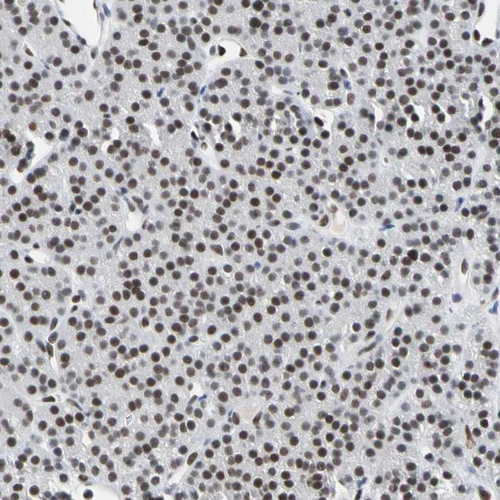

Immunohistochemical staining of human cerebral cortex, gastrointestinal, skeletal muscle and testis using Anti-FAM98B antibody HPA008502 (A) shows similar protein distribution across tissues to independent antibody HPA008320 (B).